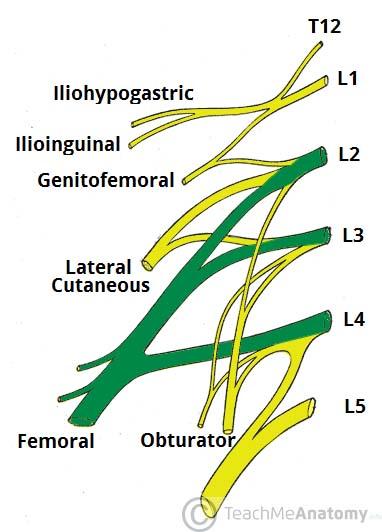

Which vertebrae join to form the lumbar plexus?

T12-L4

Which two important nerves come from the lumbar plexus?

femoral and obturator

The femoral nerve is formed from ventral rami of spinal cord levels ___________

L2-L4

The obturator nerve is formed from ventral rami of spinal cord levels ___________

L2-L4